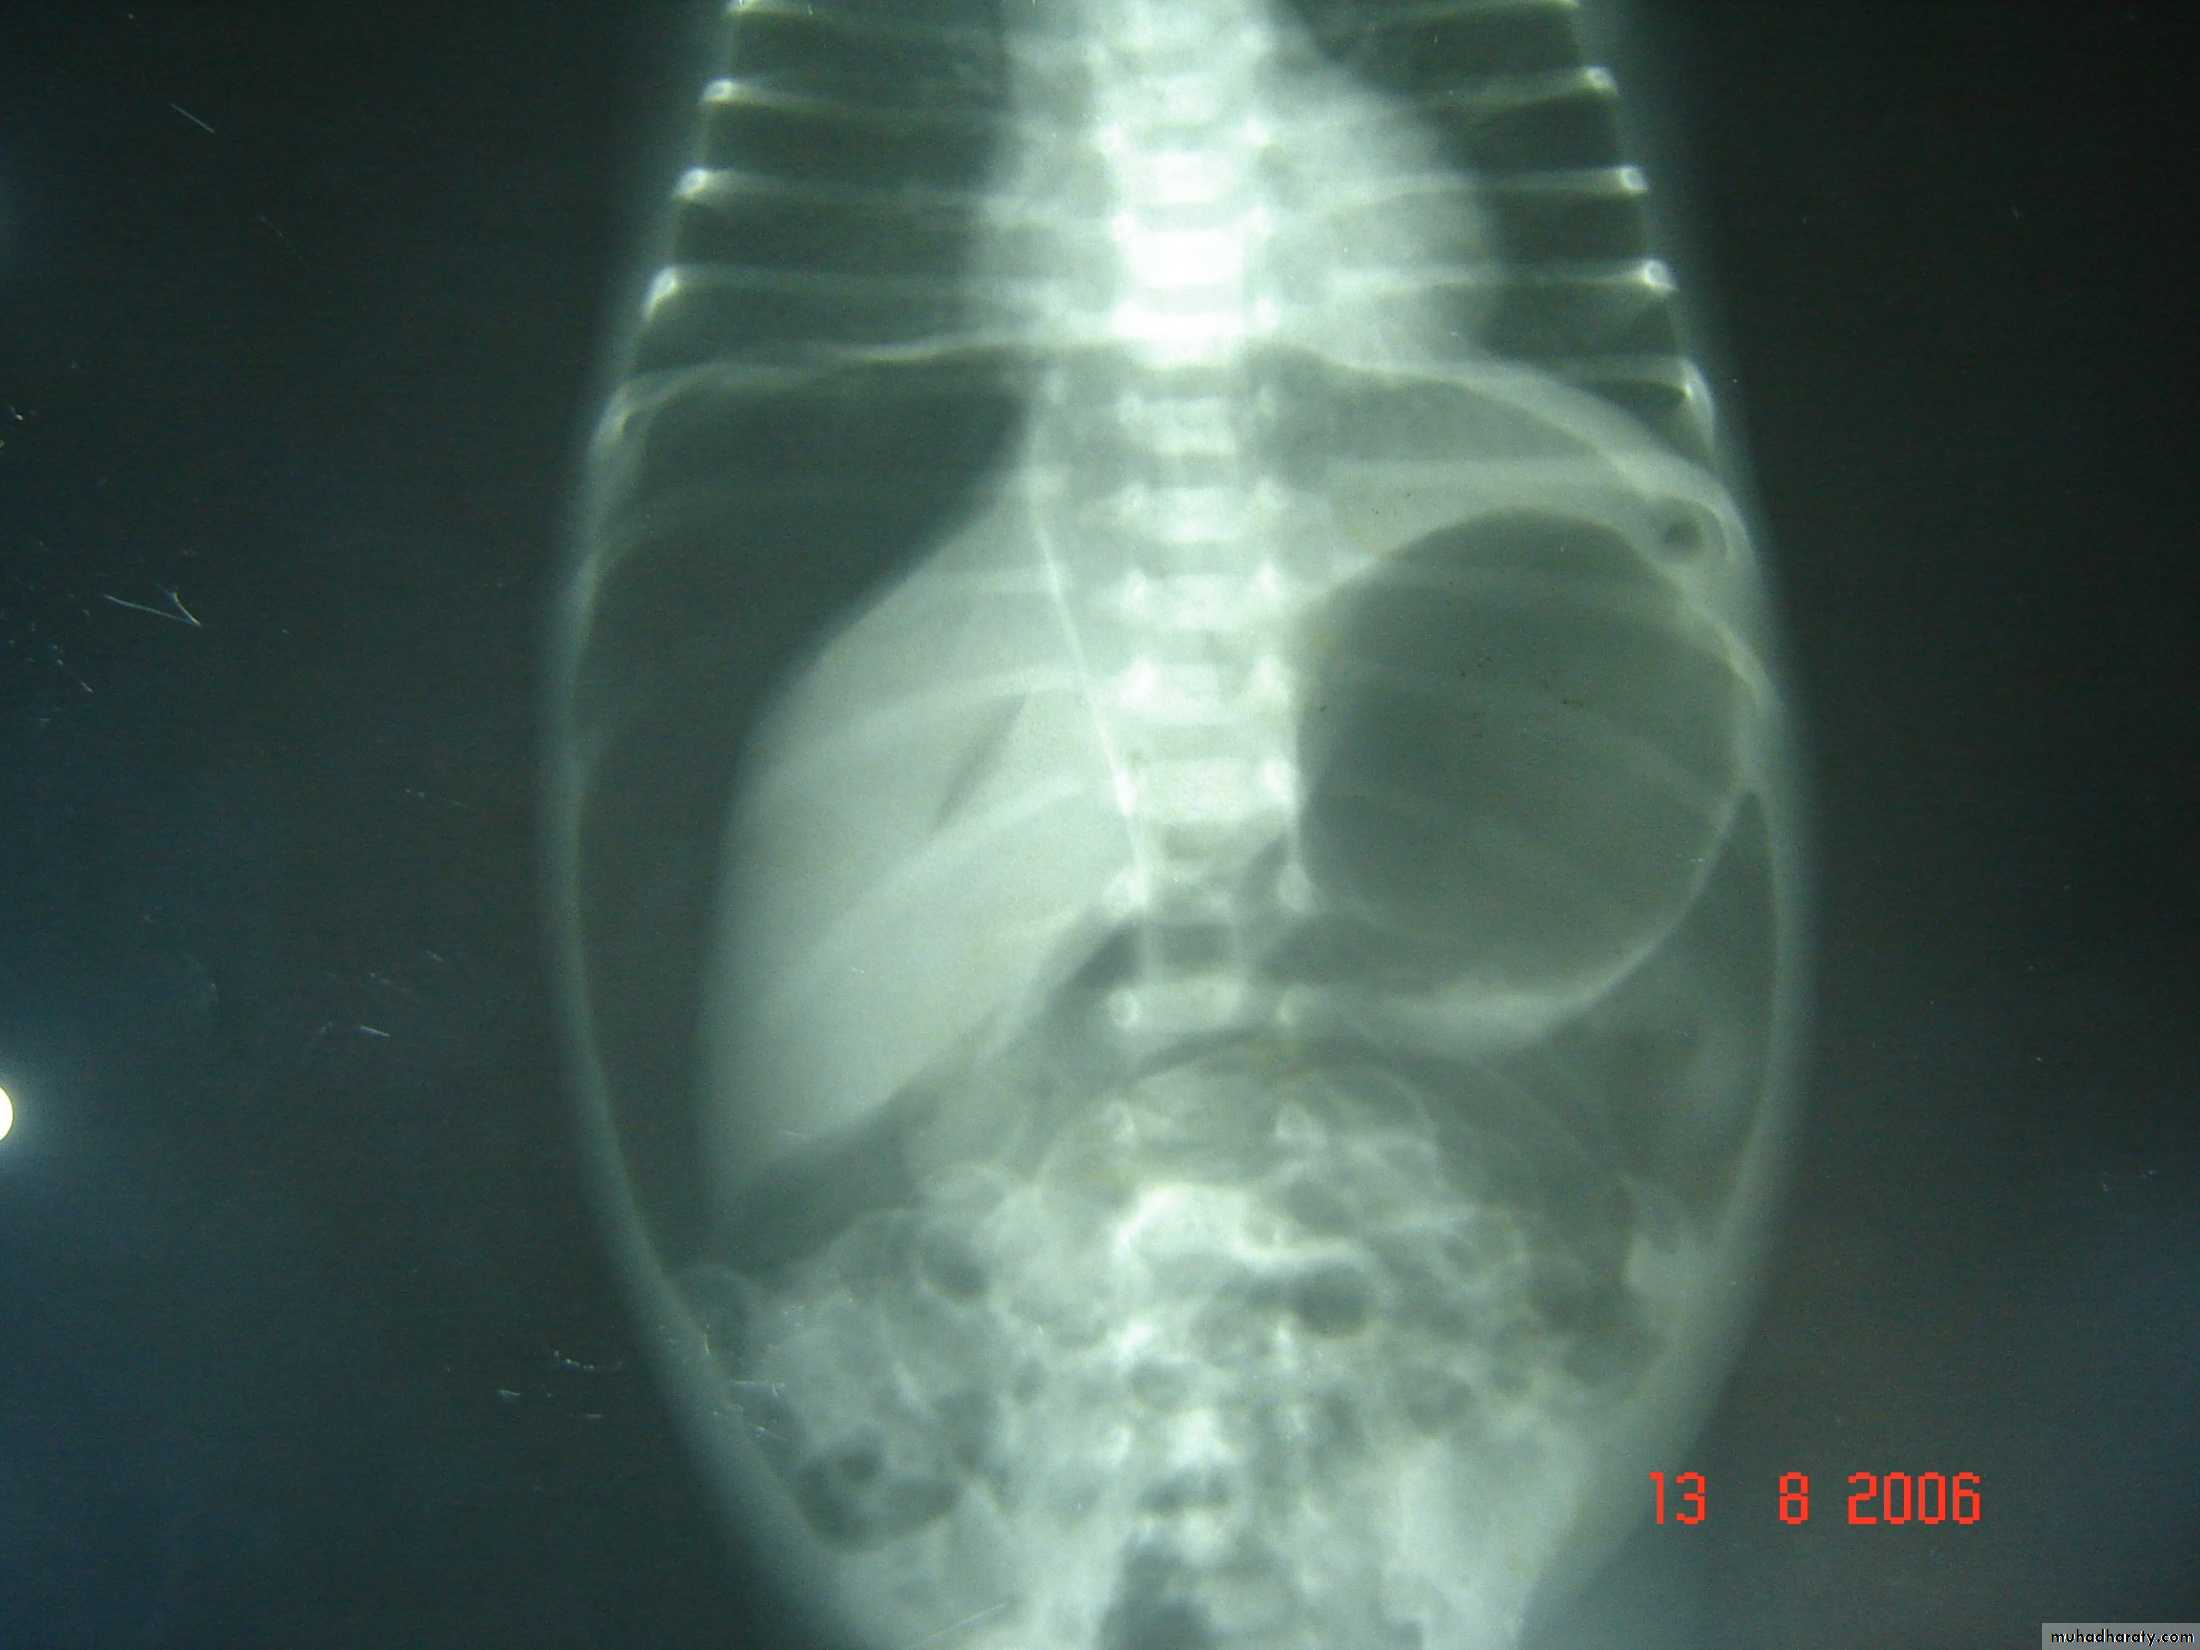

The Child with an Abdominal Mass